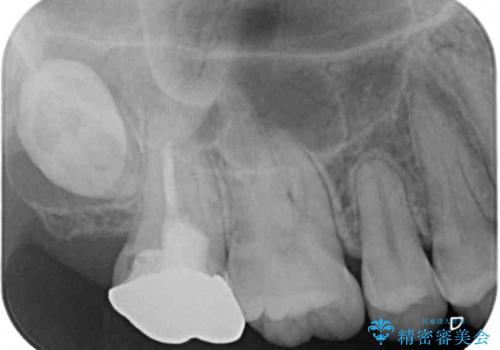

- 奥歯の銀歯に不快感が続くとのことで来院された患者様です。

銀歯の適合が悪く、汚れが溜まりやすくなっており、更には根尖の病変が認められ、咬合時に痛みがありました。

親知らずの存在により、歯肉が歯を覆っているため、親知らずの抜歯により清掃性を改善し、根管治療により痛みを取り除くこととしました。